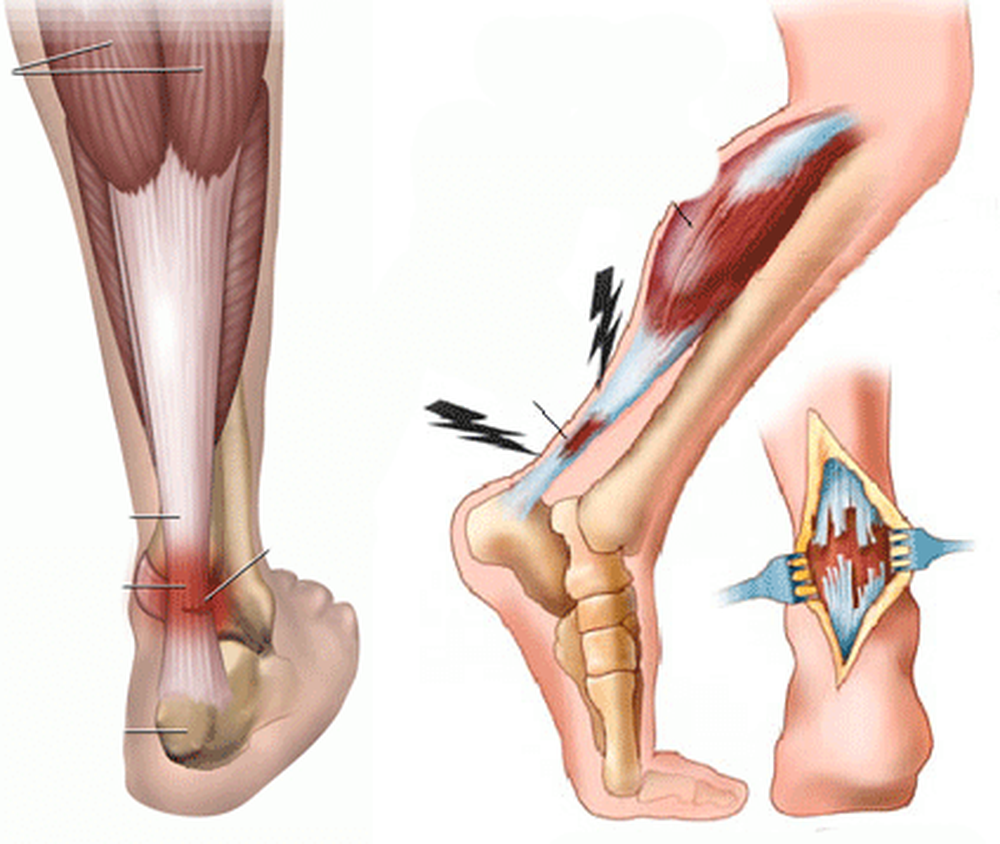

Тендинит Ахиллова сухожилия: симптомы и лечение

Раздел: Картинки на заметку